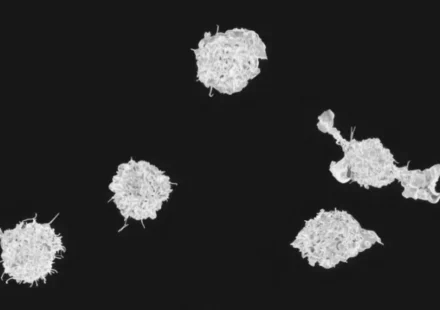

Читать далееУченые раскрыли, как 500-миллионолетняя иммунная система решает, когда атаковать

Исследователи из Пенсильванского университета обнаружили математические принципы, управляющие одной из самых древних и важных защитных систем организма — системой комплемента. Согласно новому исследованию, эта система, появившаяся более 500 миллионов лет…